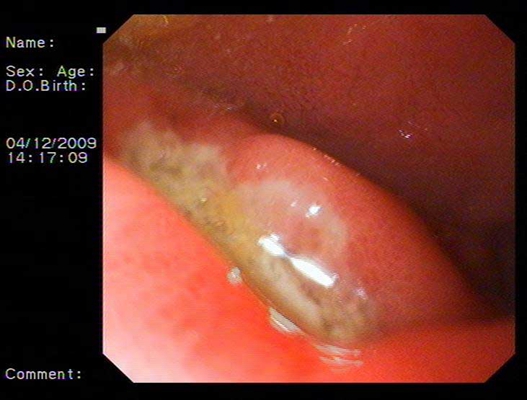

食道炎圖片